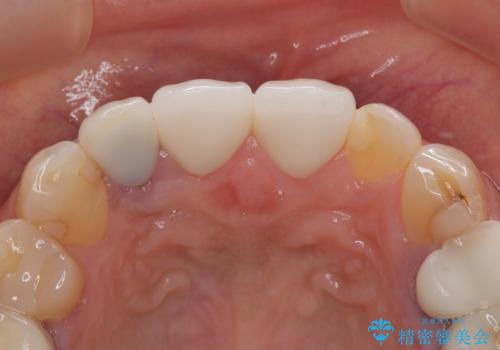

そのため当院では、上顎左右中切歯を適合精度の高いオールセラミッククラウンにて再補綴する治療をご提案し、実施いたしました。

オールセラミッククラウンは透明感が高く、自然な歯の色調に調整でき、歯と歯ぐきの境目もとても自然な仕上がりとなりました。

長期的に歯や歯周組織を守るためには、精密に適合した被せ物を入れることがとても重要です。